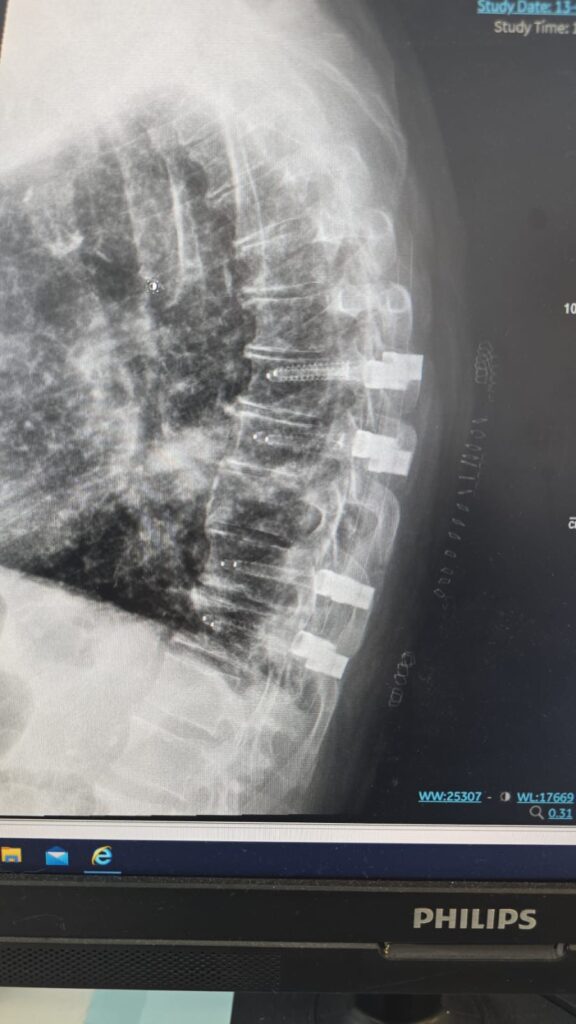

פריצת דרך רפואית כחול־לבן נרשמה השבוע בבית החולים הציבורי אסותא אשדוד: לראשונה בעולם בוצע ניתוח זעיר־פולשני לקיבוע עמוד שדרה באמצעות ברגים ומוטות מקרבון, פיתוח ישראלי פורץ דרך של חברת הסטארט־אפ CarboFix.

המטופל, גבר בן 60 שחלה בסרטן ריאה שפיתח גרורה בעמוד השדרה, הגיע למיון אסותא אשדוד כשהוא בסכנת שיתוק מיידית. במהלך הניתוח הוחדרו 8 ברגים ומוטות מקרבון בחיתוכים של כ־1 ס”מ בלבד, ובמקביל נכרת הגידול שגרם ללחץ על חוט השדרה. התוצאה הייתה דרמטית:

הטכניקה להכנסת ברגים בעמוד השדרה דרך חתכים זעירים אינה חדשה. למעשה, היא קיימת כבר כ־30 שנה ומשמשת בעיקר לטיפול בשברים בלתי יציבים. השיטה מבוססת על החדרת מחט לתוך החוליה בהנחיית שיקוף, הכנסת תיל מתכת עדין, הברגת הבורג למקומו המדויק, ולבסוף הכנסת מוט דרך אותם חתכים. השיטה מאפשרת ניתוח כמעט ללא דימום, זיהום מינימלי והחלמה מהירה.

ברגים ומוטות מקרבון אינם יוצרים הפרעות בהדמיות MRI, ומאפשרים לבצע בדיקות איכותיות גם לאחר הניתוח. בנוסף, הם מפחיתים משמעותית סיכונים בהקרנות-ומאפשרים לרופא האונקולוג לכוון את הקרינה בדיוק רב יותר.